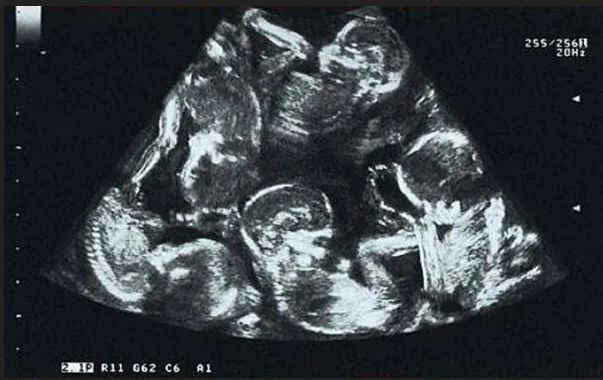

Podczas pierwszych badań USG Alexandra dowiedziała się, że jest w ciąży mnogiej, co samo w sobie już było dużym zaskoczeniem. Z początku lekarze sądzili, że kobieta spodziewa się trojaczków.

Jednak z każdym kolejnym badaniem liczba dzieci rosła, aż w końcu usłyszeli niezwykłą wiadomość - na świat przyjdą pięcioraczki. Było to niezwykłe wydarzenie nie tylko dla samej rodziny, ale również dla całych Czech ponieważ Alexandra została pierwszą mamą pięcioraczków w historii kraju.

Wkrótce po ogłoszeniu tej informacji, zdjęcia z badań USG trafiły do mediów społecznościowych, a o Alexandrze zaczęto mówić w całej Europie. Narodziny pięcioraczków były planowane na czerwiec 2013 roku i mimo że ciąża była wysokiego ryzyka, dzieci przyszły na świat bez większych komplikacji.